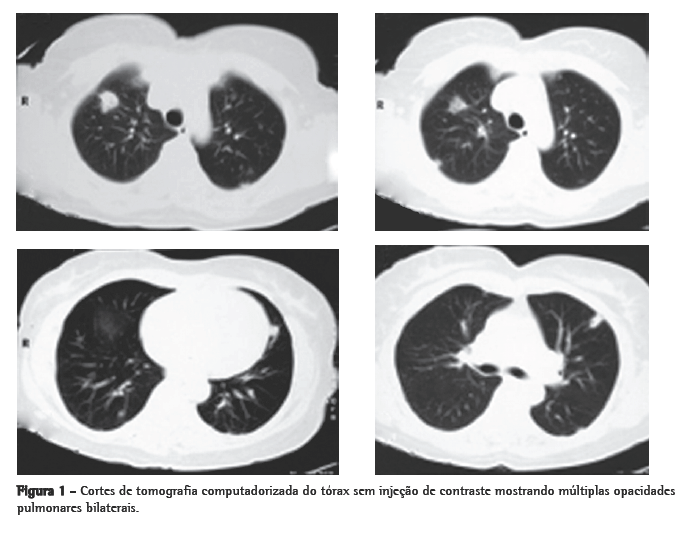

A tomografia computadorizada de tórax de controle após este curso de antibióticos mostrou regressão praticamente total das opacidades (Figura 2). Permaneceu afebril desde o terceiro dia do novo curso de antibióticos. Nenhum microrganismo foi isolado das hemoculturas e culturas do lavado broncoalveolar. A anticoagulação foi suspensa após 20 dias de uso, pela falta de evidência de benefício na síndrome de Lemierre.

Abstract Lemierre's syndrome is characterized by acute oropharyngeal infection, complicated by internal jugular venous thrombosis secondary to septic thrombophlebitis, and by metastatic infections in various distant organs-most commonly in the lungs. We report a case of Lemierre's syndrome in a 56-year-old female who presented with right-sided neck mass and fever. Right internal jugular venous thrombosis was demonstrated on an ultrasound. A computed tomography scan of the chest revealed multiple opacities throughout both lungs. An open surgical biopsy was performed due to suspicion of pulmonary metastases. Anatomopathological examination revealed septic emboli in lung parenchyma. Retrospectively, the patient reported a history of pharyngitis two weeks prior to hospitalization. After the diagnosis had been made, the patient was treated with broad-spectrum antibiotics (cefuroxime for 7 days and azithromycin for 5 days; subsequently, because fever persisted, cefepime for 7 days). One month later, a computed tomography scan of the chest revealed resolution of the opacities.

A síndrome de Lemierre é caracterizada pela infecção aguda da orofaringe, complicada por trombose venosa jugular interna secundária à tromboflebite séptica, e por infecções metastáticas a vários órgãos distantes-mais freqüentemente os pulmões. Relatamos um caso de síndrome de Lemierre em uma mulher de 56 anos que se apresentou com massa cervical à direita e febre. Trombose venosa jugular interna foi demonstrada na ecografia. A tomografia computadorizada de tórax revelou múltiplas opacidades em ambos os pulmões. Uma biópsia pulmonar cirúrgica foi realizada por suspeita de metástases pulmonares. O exame anatomopatológico revelou êmbolos sépticos em parênquima pulmonar. Retrospectivamente, a paciente relatou história de faringite duas semanas antes da hospitalização. Após o diagnóstico, foi tratada com antibióticos de amplo espectro (cefuroxima por 7 dias e azitromicina por 5 dias e, posteriormente, devido à persistência de febre, cefepime por 7 dias). A tomografia computadorizada de tórax, realizada um mês após, mostrou resolução das opacidades.